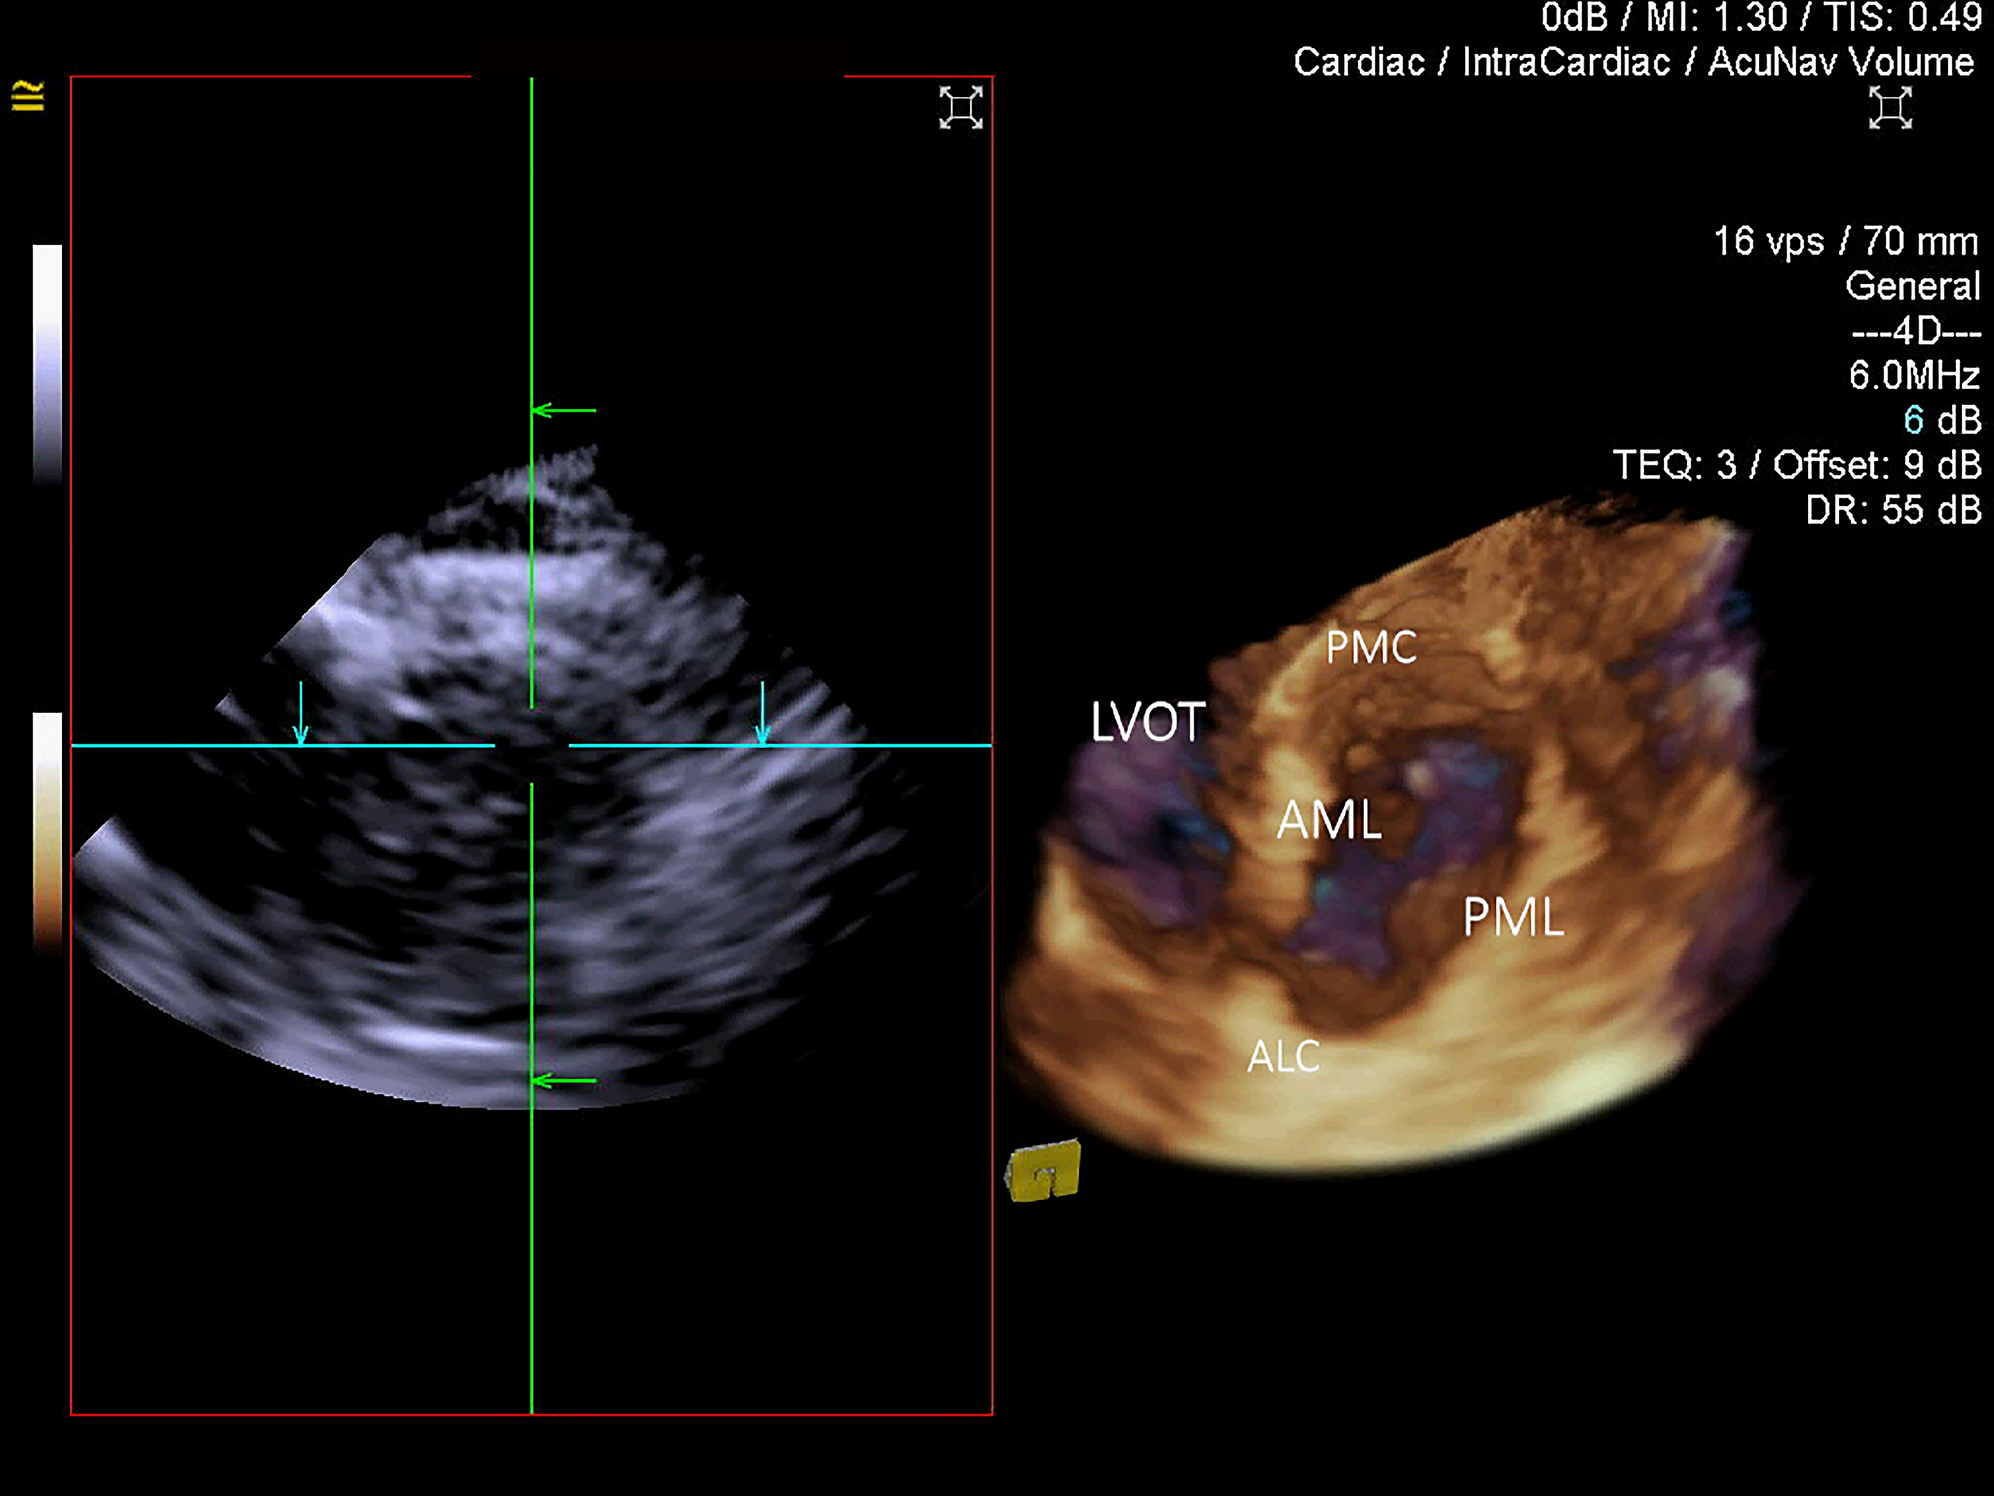

Figure 4

3D ICE en-face ventricular view of the mitral annulus and mitral valve. LVOT left ventricular outflow tract, AML anterior mitral leaflet, PML posterior mitral leaflet, ALC anterolateral commissure, PMC posteromedial commissure.